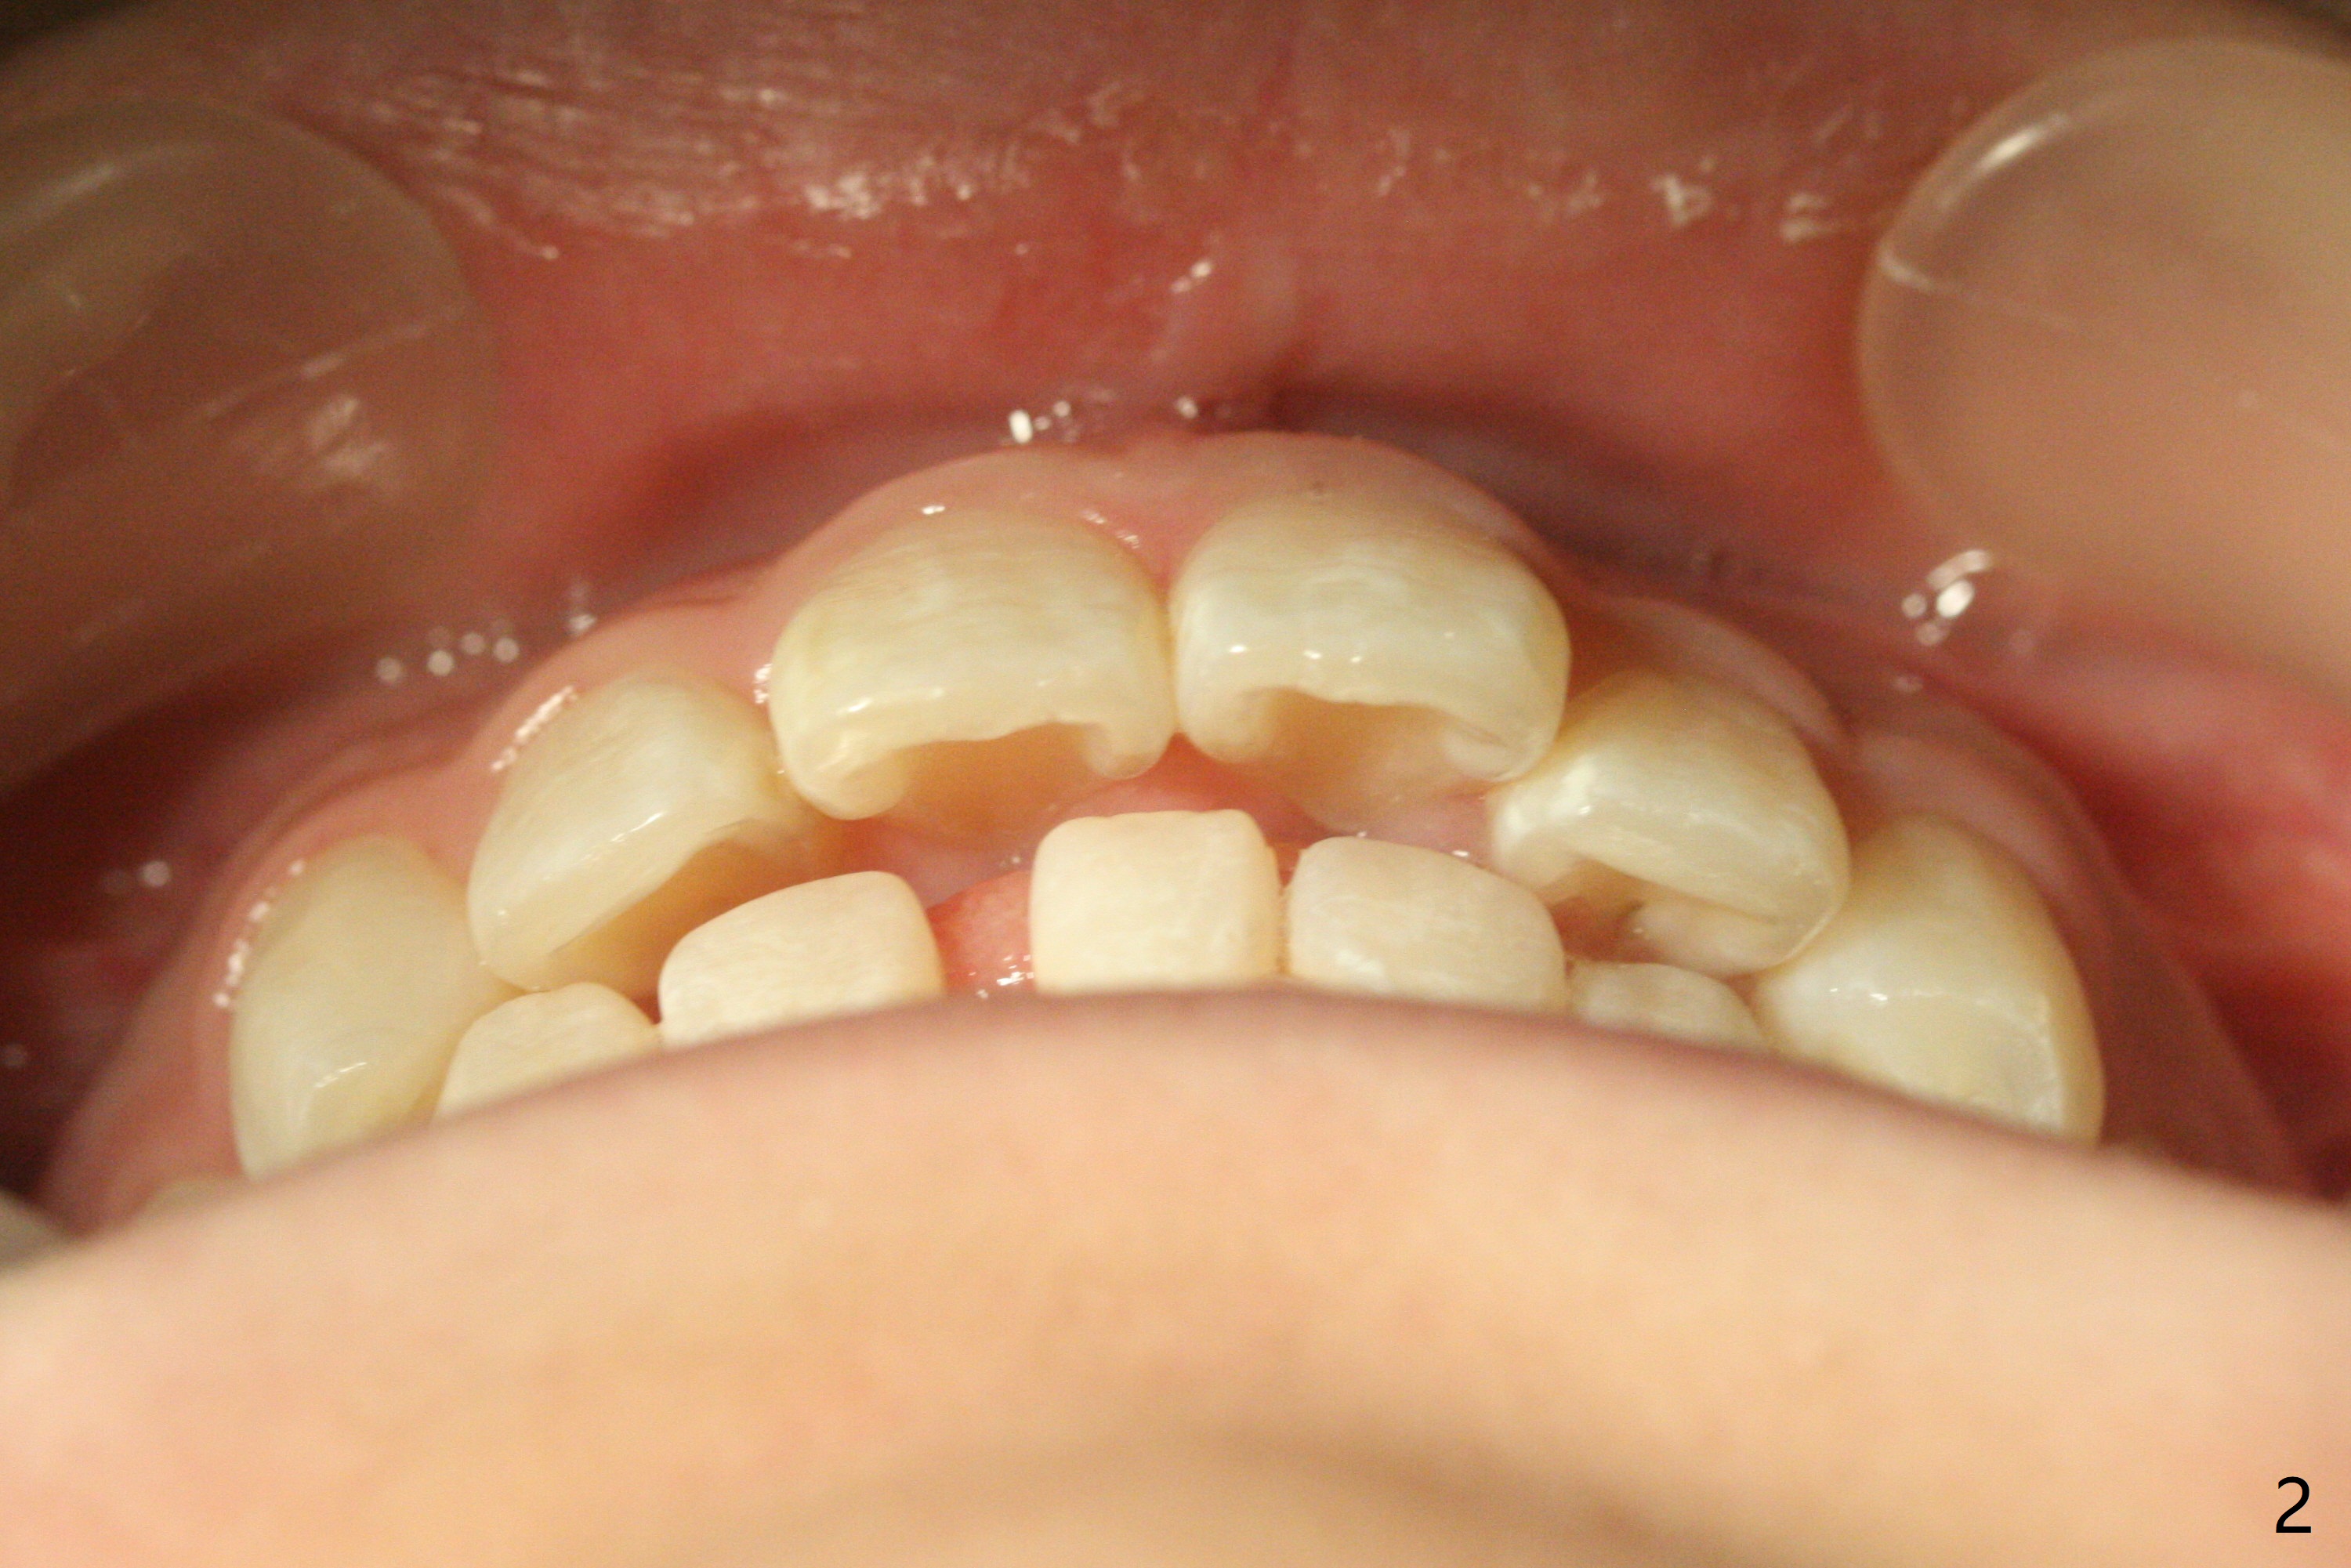

13岁女孩面型正常,先天性缺失右下1(图一,四,七),前牙深覆盖(图二),邻牙扭转(图三),治疗计划使用隐形矫正器,上牙片切,内收,关闭下切牙间隙(图八)。片切前发现上切牙邻面龋(图五,六),最大一个已经修补(右上2),不知其余小的龋坏能否片切,涂氟保守处理?不过她有龋坏易感性,以前乳牙龋坏。邻面片切后,上,下颌分别用无色和蓝色树脂做attachments(图九)。不明白的是Reciprocating saw远不如wheel利索。